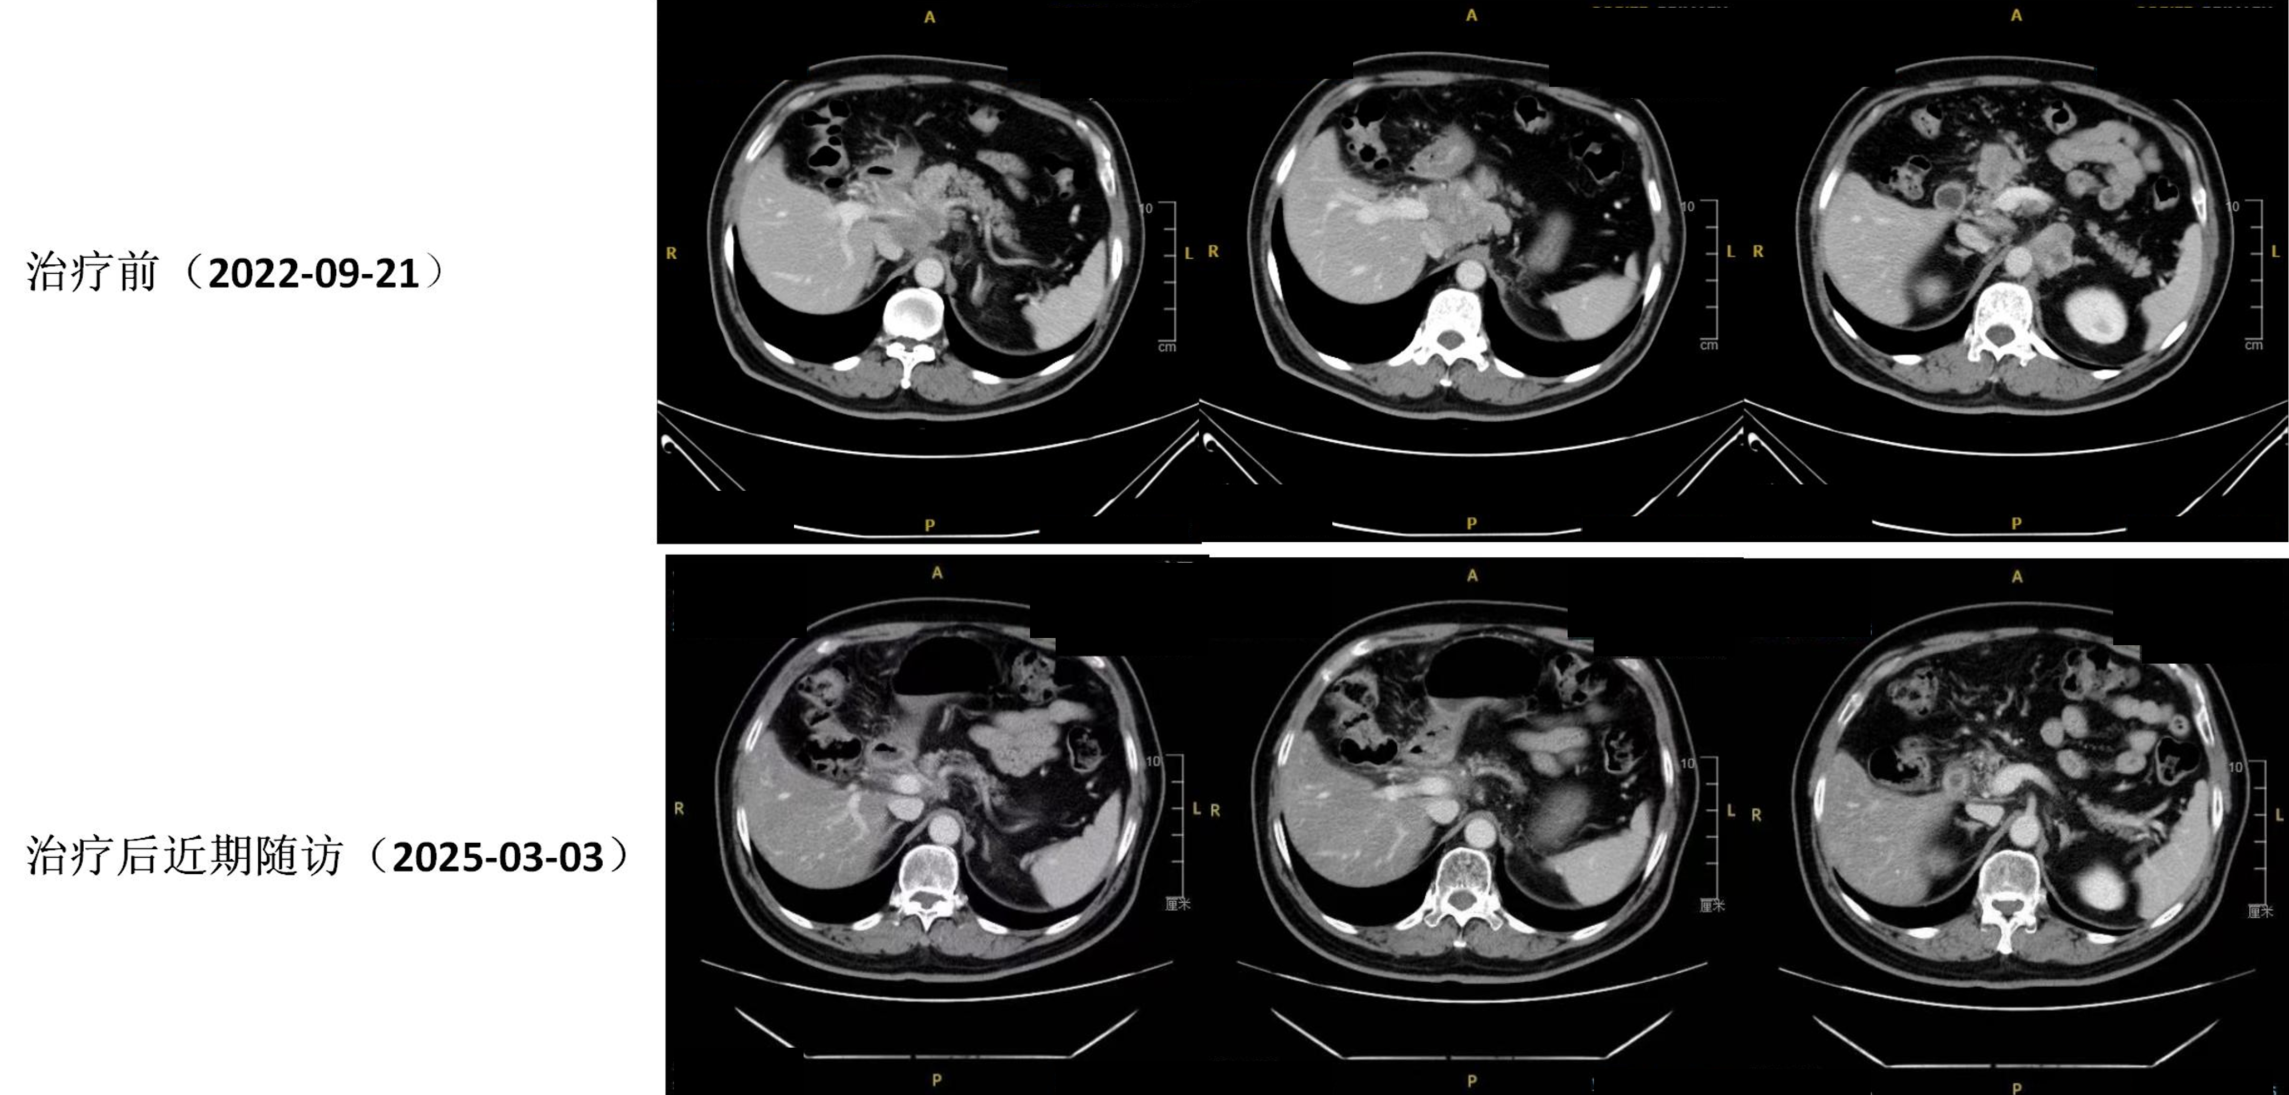

定期影像评估,至2025年03月03日病情稳定。

CT复查(2025年03月03日):胃窦壁局部稍显增厚,黏膜面强化尚可,较前变化不大;胰颈软组织肿块目前轮廓显示仍不明确,局部稍显致密;瘤旁、肝门区、肠系膜根部多发肿大淋巴结较前大致相仿。

11.jpg

图7. 首治前(2022年09月21日)与近期随访(2025年03月03日)CT对比